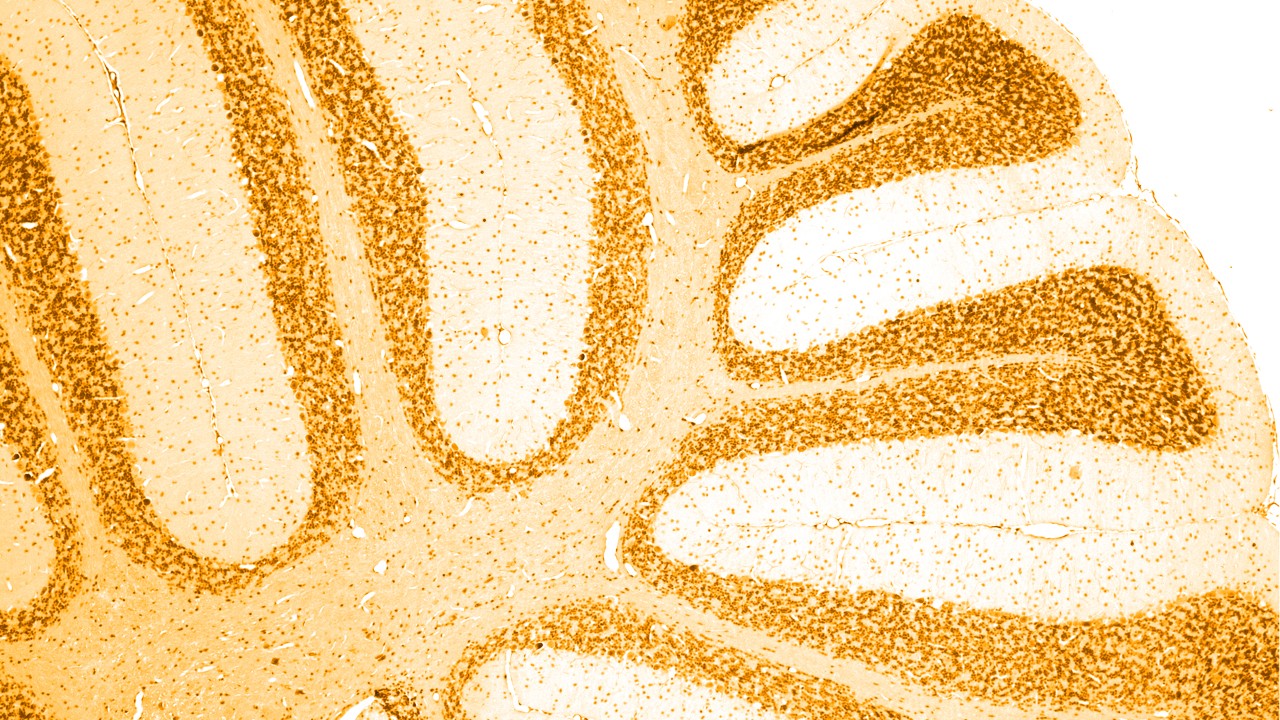

Los trastornos neurológicos son enfermedades del sistema nervioso central y periférico. En otras palabras, el cerebro, la médula espinal, los nervios y los músculos que regulan y coordinan la actividad corporal.

Existen numerosas causas diferentes de demencia, de las cuales la más común es la enfermedad de Alzheimer, la cual está relacionada con la acumulación de “placas amiloides” anormales y “ovillos neurofibrilares” en el cerebro. Otros tipos de demencia también tienen una acumulación anormal de proteínas Tau en el cerebro; a este grupo de padecimientos se denomina " tauopatías".